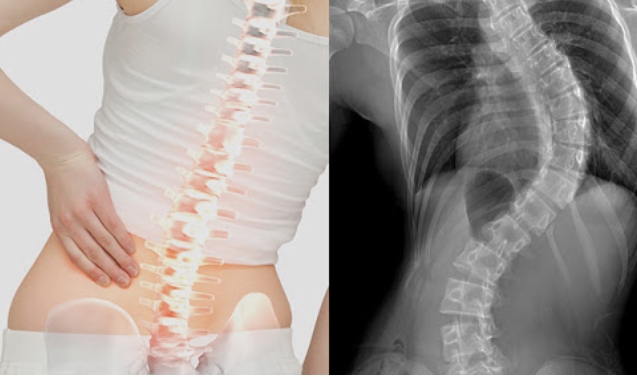

척추측만증환자 해마다 증가하고 있다고 합니다. 원인은 잘못된 자세로 장시간 앉아있기 때문이라합니다.

척추측만증은 척추가 휘어져 몸의 균형이 틀어진것을 말합니다.

통증과 함께 심폐기능 이상을 유발할 수 있습니다. 대표적인 치료방법은 척추측만증 교정운동입니다.